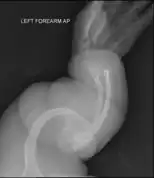

The main symptom of osteogenesis imperfecta is fragile, low mineral density bones; all types of OI have some bone involvement.[5] In moderate and especially severe OI, the long bones may be bowed, sometimes extremely so.[28] The weakness of the bones causes them to fracture easily—a study at the Endocrine Unit at the National Institute of Child Health in Karachi, Pakistan found an average of 5.8 fractures per year in untreated children.[29] Fractures typically occur much less after puberty, but begin to increase again in women after menopause and in men between the ages of 60 and 80.[1]: 486

OI type III causes osteopenic bones that fracture very easily, sometimes even in utero, often leading to hundreds of fractures during a lifetime;[24] early scoliosis that progresses until puberty; dwarfism (a final adult height frequently less than 4 feet or 120 centimetres); loose joints; and possible respiratory problems due to low rib cage volume causing low lung volumes.[5]: 1512

- Type V – Having the same clinical features as type IV, it can be clinically distinguished by observing a "mesh-like" appearance to a bone biopsy under a microscope. Type V can be further distinguished from other types of OI by the "V triad": an opaque band (visible on X-ray) adjacent to the growth plates; hypertrophic calluses (abnormally large masses of bony repair tissue) which form at fracture sites during the healing process; and calcification of the interosseous membrane of the forearm,[50] which may make it difficult to turn the wrist.[1]: 429 Other features of this condition may include pulled elbow, and, as in other types of OI, long bone bowing and hearing loss.[64] Cases of this type are caused by mutations in the IFITM5 gene on chromosome 11p15.5.[64][49] The separation of type V from type IV OI, its clinical type, was initially suggested even before its genetic cause was known, by Glorieux et al. in 2000.[50][65] Type V is relatively common compared to other genetically defined types of OI—4% of OI patients at the genetics department of the Brazilian Hospital de Clínicas de Porto Alegre were found to have it.[66]